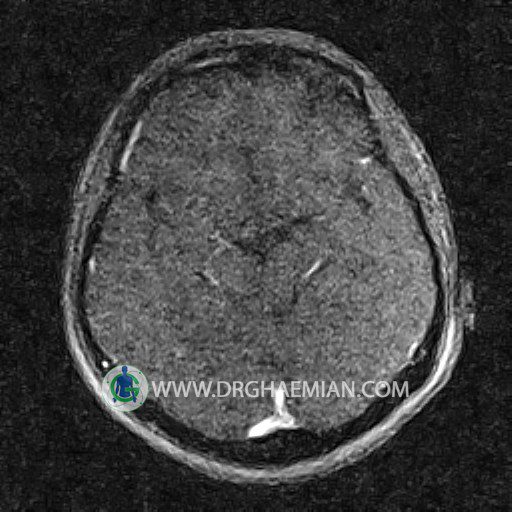

ام آر وی یک روش تصویربرداری دقیق و غیر تهاجمی است که برای معاینه ورید های بدن و ارزیابی سلامت رگ ها استفاده می شود. ورید ها خون را از اعضای بدن به قلب باز می گرداند تا دوباره اکسیژن و مواد مغذی به خون داده شود. ام آر وی جریان خون را ارزیابی و موارد غیرعادی مضر مانند لخته های خونی را شناسایی می کند. در این کیس ترومبوز دیواری مغز در سینوس عرضی راست و ترمبوز جزئی در سینوس عرضی چپ دیده می شود.

Images of the venous cranial vessels demonstrates a superior sagittal sinus of normal caliber with normal arrangement of draining superficial cerebral veins.

The great cerebral vein Galen inferior sagittal , straight sinus and left sigmoid sinus appear normal.

The right sigmoid sinus present a normal caliber.

The other evaluable deep cerebral veins , basal and labbe are normally developed and patent.

The other evaluable portions of the neurocranium show no abnormalities.

– Narrowing of left transverse sinus with filling defect & inthimal irregularity

suggestive for partial thrombosis

– Inthimal irregularity in anterior wall of right transverse sinus suggestive for mural thrombosis

are seen